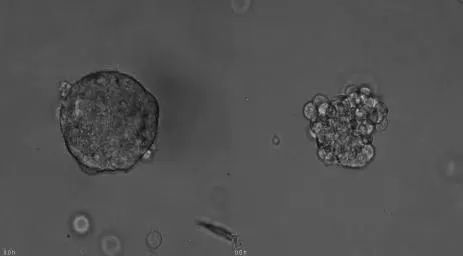

肿瘤类器官,则是指从患者身上取出癌细胞,在实验室体外培养出具备三维结构的微器官,形成肿瘤的“替身”,也就是肿瘤类器官。肿瘤类器官无论是在遗传学背景还是组织学特征上,都与患者自身的肿瘤高度相似。

肿瘤类器官作为患者的“试药替身”,具有高通量、易操作的特性,在短时间(平均两周)获得化疗药、靶向药、单抗药、联合用药等的敏感性检测结果,为无药可用、多药可用的肿瘤患者争取更多宝贵治疗时间,为用药方案的制定提供更精准的数据支撑。

类器官